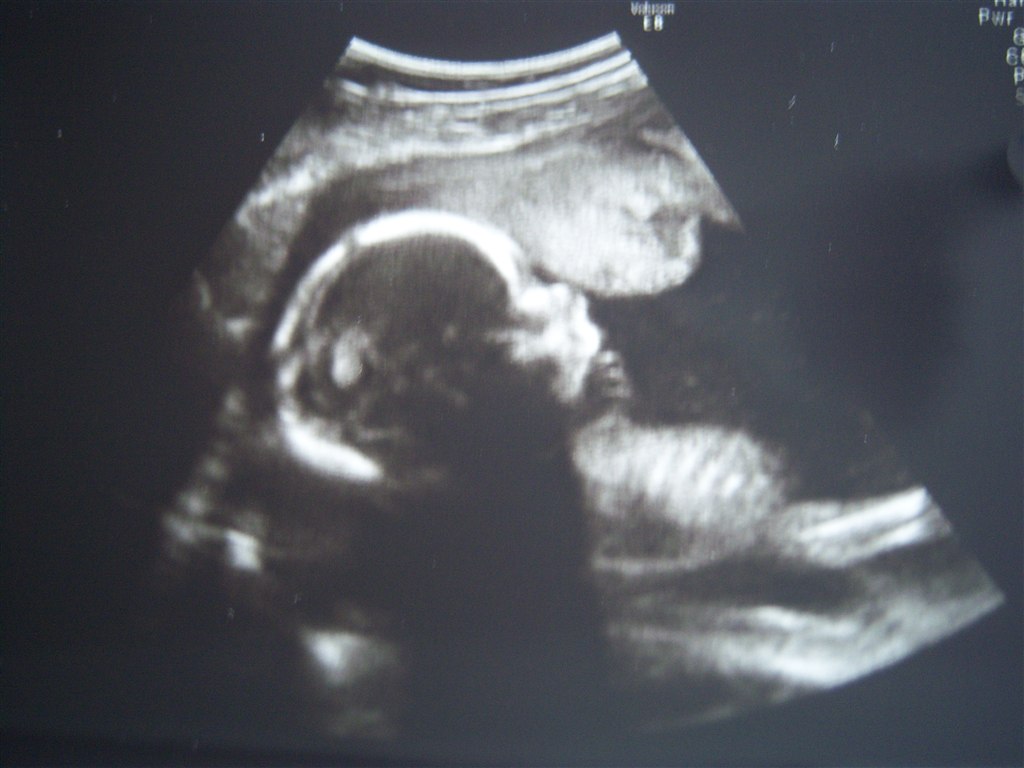

Så har vi været til Misdannsesscanning i dag! Hvor var det bare dejligt at se den lille bebs, som viste sig at være en lille dreng  Han var super fin, og vi fik også lidt billeder med hjem! og vi fik ændret terminsdatoen til 24. August. Så det betyder at jeg er halvvejs i dag  Jeg har nu også kunne mærke ham i nogle uger efterhånden, og farmand har også mærket ham sparke.

Mange tak  Det er lidt utydeligt billede, i forhold til da vi så ham på skærmen.

Vedhæftede fotos (klik for at se i fuld størrelse)